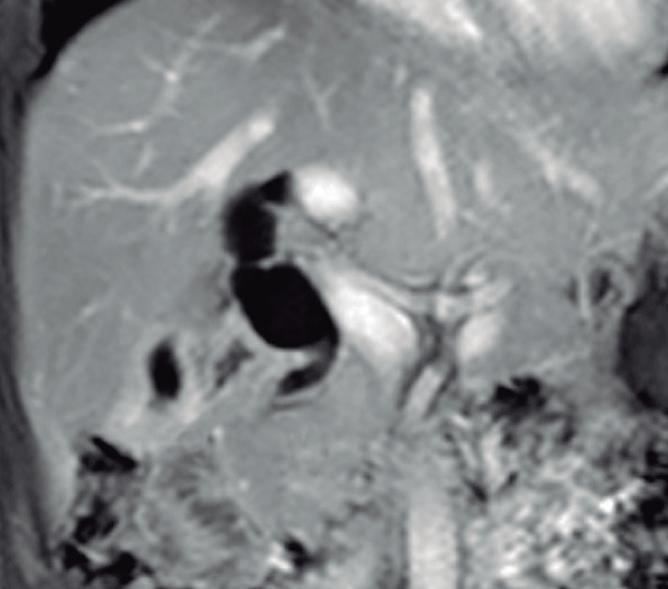

Los individuos con páncreas divisum suelen ser asintomáticos y diagnosticados incidentalmente en estudios de colangio-RM realizados por otros motivos (Figura 3). Se ha descripto su potencial rol como desencadenante de eventos de pancreatitis aguda (PA) y pancreatitis aguda recurrente (PAR). La hipótesis es que la papila menor, más pequeña, es insuficiente para permitir el drenaje adecuado del volumen de secreciones originadas en el páncreas corpocaudal, que habitualmente derivan hacia la papila mayor. Actualmente se acepta que la PAR es

una condición de origen multifactorial y que el páncreas divisum actúa como cofactor, habitualmente asociado a otras entidades, como son las mutaciones genéticas (genes CFTR, PRSS1). La sola presencia de páncreas divisum como “gatillo” de pancreatitis es controversial, fundamentalmente debido a que no se ha demostrado mayor prevalencia de esta condición en pacientes con PA, comparativamente con la población general.8, 9 En la colangio-RM podemos encontrar algunos elementos imagenológicos que sugieren un posible au-

Figura 3. Páncreas divisum. Colangiopancreatografía por resonancia magnética

A) Subtipo 1. Las flechas señalan al conducto pancreático principal, que drena sus secreciones en la papila menor. La cabeza de la flecha señala el conducto de Wirsung desembocando en la papila mayor. B) Subtipo 2. CPP desembocando en la papila menor en ausencia de un conducto definido del páncreas ventral. C) Subtipo 3. La flecha señala una diminuta comunicación entre los conductos del páncreas dorsal y ventral.

mento de la presión del CPP y por lo tanto una mayor influencia del páncreas divisum como factor etiológico de pancreatitis. La dilatación ductal mayor a los 3 mm y/o la presencia de una dilatación sacular en la desembocadura (Santorinicele), son hallazgos imagenológicos

que sugieren un rol en el desarrollo de eventos (Figuras 4 y 5). Por otra parte, la colangio-RM, por su gran resolución de tejidos, puede demostrar signos incipientes de pancreatitis crónica que orienten hacia el potencial impacto del páncreas divisum.10-13